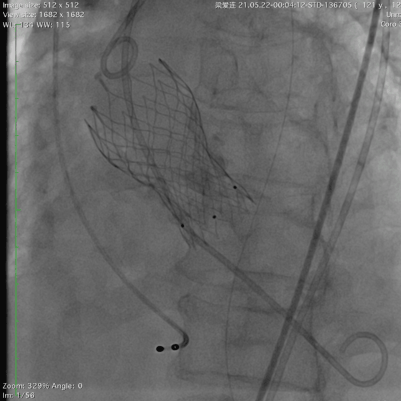

78岁的阿婆,入院3年余前出现活动后胸闷,气促。3天前出现恶心,呕吐,双下肢水肿,来我院急诊科就诊,行心脏彩超提示为重度主动脉瓣狭窄并中度关闭不全,经郭惠明主任团队评估后收住入院,拟行TAVR治疗,阿婆急性心衰,呼吸急促,循环不稳,我院ICU团队立刻对患者进行抢救处理,紧急气管插管,循环不稳定,大剂量血管活性药物维持,尿少,乳酸持续升高,命悬一线。郭惠明刘健主任团队立刻对患者施行紧急救治,23点40麻醉,00:30开始手术,01:27分手术结束,整个手术过程持续不到1小时。患者术后3小时清醒,1天后撤出呼吸机,血管活性药物基本减停,生命体征恢复稳定。

最终造影(狭窄解除,没有瓣周漏)